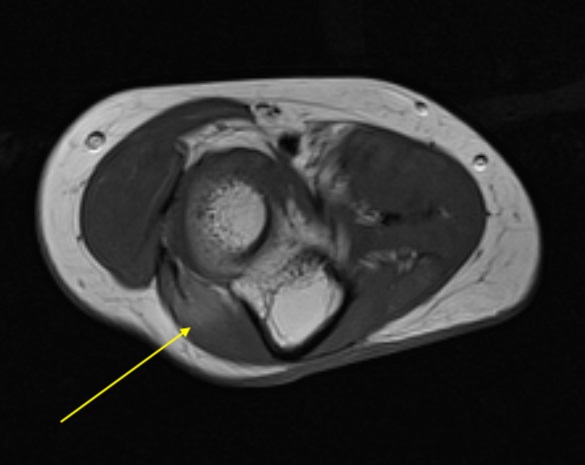

Ahora te enseño las imágenes de la resonancia; primero ancóneo normal señalado con flecha amarilla, recuerda, en el epicóndilo lateral…

Ahora el ancóneo accesorio o epitroclear, recuerda, en la epitróclea: